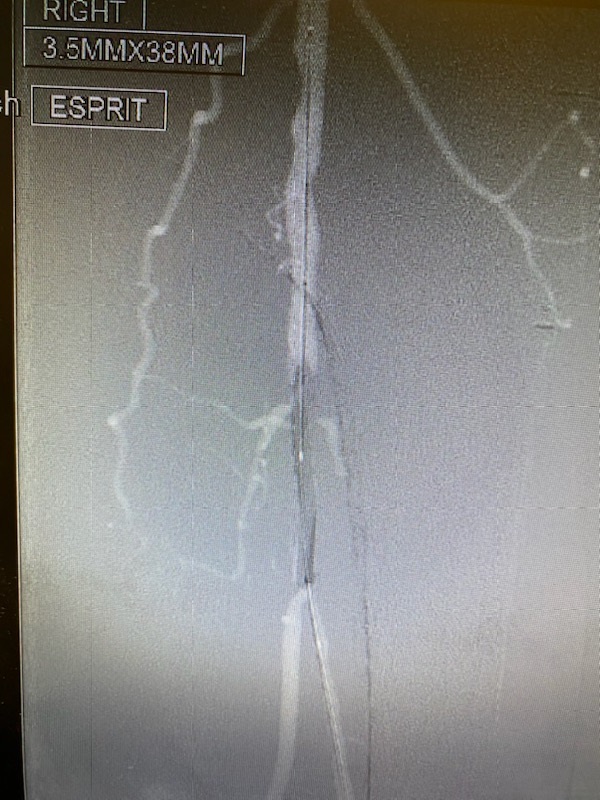

Dr. George DeKornfeld has become the second surgeon in Pennsylvania to successfully utilize EspritTM—a revolutionary new technology designed to treat lower extremity peripheral artery disease (PAD). This innovative system, the first of its kind, helps keep arteries open while delivering everolimus, a drug that promotes healing. The stent then dissolves over time, leaving the artery supported and healthier.

The EspritTM Below the Knee System, approved by the FDA in 2024, uses dissolving materials similar to surgical sutures. After the device is implanted through a catheter-based procedure, it opens blocked arteries and supports healing before dissolving. This offers a promising new option for patients facing severe PAD.